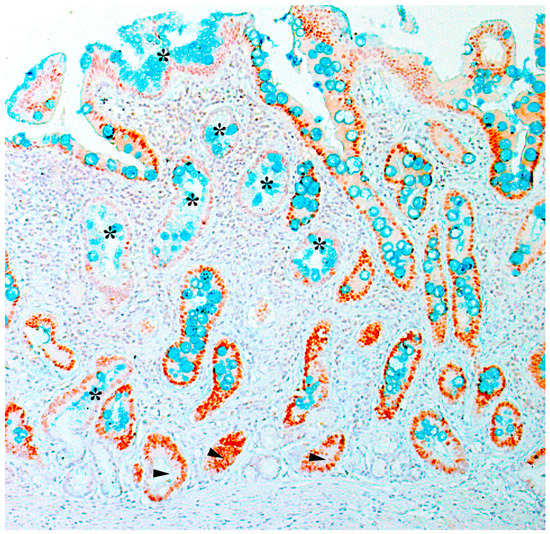

| Marker | Functional Role | Normal Expression | Expression in Pathological Condition | Associated Metaplasia |

|---|---|---|---|---|

| MUC1 | formation of mucosal protective barrier | foveolar epithelium of the body and antrum of the stomach | lack of expression | positive expression in incomplete intestinal metaplasia |

| MUC2 | formation of mucosal protective barrier | goblet cells | goblet cells of metaplastic epithelium | complete intestinal metaplasia |

| MUC5AC | formation of mucosal protective barrier | foveolar epithelium of the body and antrum of the stomach | lack of expression | pseudopyloric metaplasia positive expression in incomplete intestinal metaplasia |

| MUC6 | formation of mucosal protective barrier | lower part of antral glands and neck cells | similar to TFF2 | pseudopyloric and incomplete intestinal metaplasia |

| CDX2 | intestinal transcription factor | absent | cell nuclei in glands, which are transformed to intestinal metaplasia | intestinal metaplasia |

| Hep | urea metabolism | hepatocytes, small intestinal epithelium | cells of metaplastic glands | incomplete intestinal metaplasia |

| CD44v9 | cell adhesion factor | absent | cytoplasm and membrane of damaged epithelial cells | SPEM |

| SOX9 | transcription factor | neck of the gastric glands of the antrum | basal part of metaplastic glands | intestinal metaplasia, SPEM |

| TFF2 | Formation of mucosal barrier of the stomach | mucocytes of neck of the gastric glands of the body of the stomach, lower part of of antral glands | cytoplasm of mucocytes of metaplastic glands | SPEM |

| TFF3 | formation of mucosal protective barrier | goblet cells | in goblet cells of metaplastic glands | intestinal metaplasia |

| AQP5 | water-channel protein | lower part of antral glands, stem cells | increase expression | pseudopyloric metaplasia, SPEM, intestinal metaplasia |